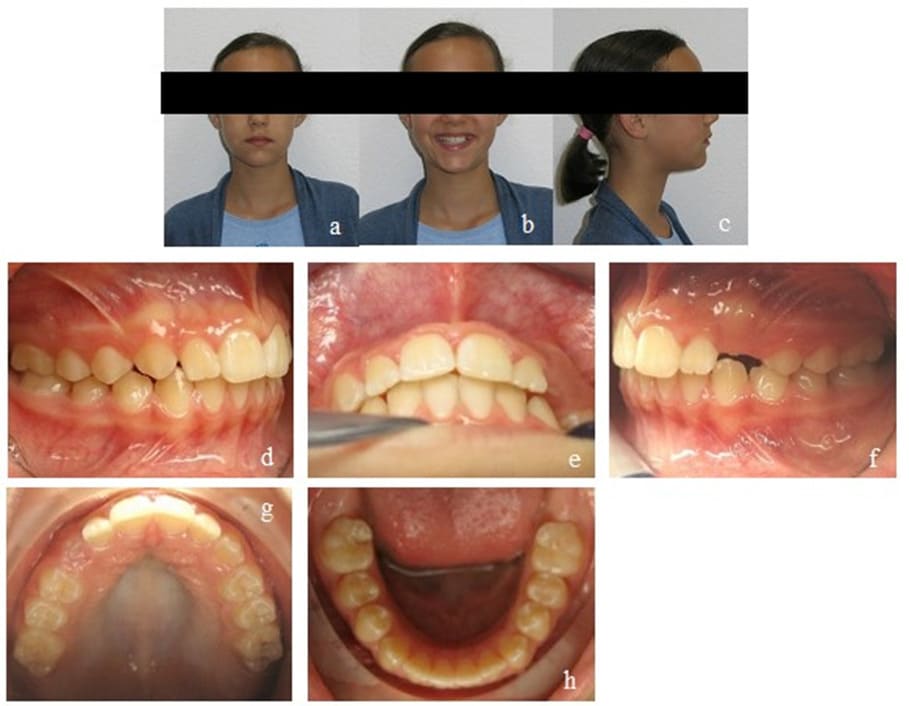

During all treatment phases, the patient had been highly compliant and motivated. 18 months of active mykie®-treatment showed significant improvements on the dental as well as on the myofunctional side. To ensure a stable retention of what was achieved, the patient continued wearing an EGA on a nightly basis throughout the transitional phase of dentition until all second molars erupted and visited the orthodontic office biannually. No further orthodontic treatment was necessary (Figure 8). Finally, for perfect alignment, a short aligner treatment could be recommended (Figure 9).

Figure 8: Case 1. Final findings. Frontal view of the occlusion (b), occlusion right (a) and left (c). Upper (d) and lower arch (e).

Figure 9: Case 1. Final findings after a short Invisalign® treatment. En face (a, b) and profile of the patient (c). Final Panoramic x-ray (d). Frontal view of the occlusion (f), occlusion right (e) and left (g). Upper (h) and lower arch (i). View of the final overjet and overbite (j).

Case 2 - Cross Bite/ Open Bite

This patient was transferred to our orthodontic office by her speech-therapist at the age of 6. During initial diagnosis, a unilateral posterior cross bite on the right side and an anterior open bite of 3 mm were apparent. Accordingly, the upper arch was too narrow and needed further transversal development. Mild crowding in the lower front segment and an exaggerated Wilson’s curve of the lower permanent and deciduous molars could be seen. The dental situation confirmed the myofunctional diagnosis of a habitual open mouth posture, infantile swallowing, a low resting position of the tongue and enlarged palatine tonsils. Nasal polyps had already been removed at an earlier stage (Figure 10).

Figure 10: Case 2. Initial findings. En face (a, b) and profile of the patient (c). Frontal view of the occlusion (e), occlusion right (d) and left (f). Upper (g) and lower arch (h). Initial Panoramic x-ray (i).

Our initial orthodontic goal was the posterior cross bite elimination by maxillary expansion to create enough space for the tongue. The second goal was to straighten up the lower molars and to close the anterior open bite. Myofunctional goals comprised the establishment of nasal breathing, mature swallowing, and the physiological resting position of the tongue.